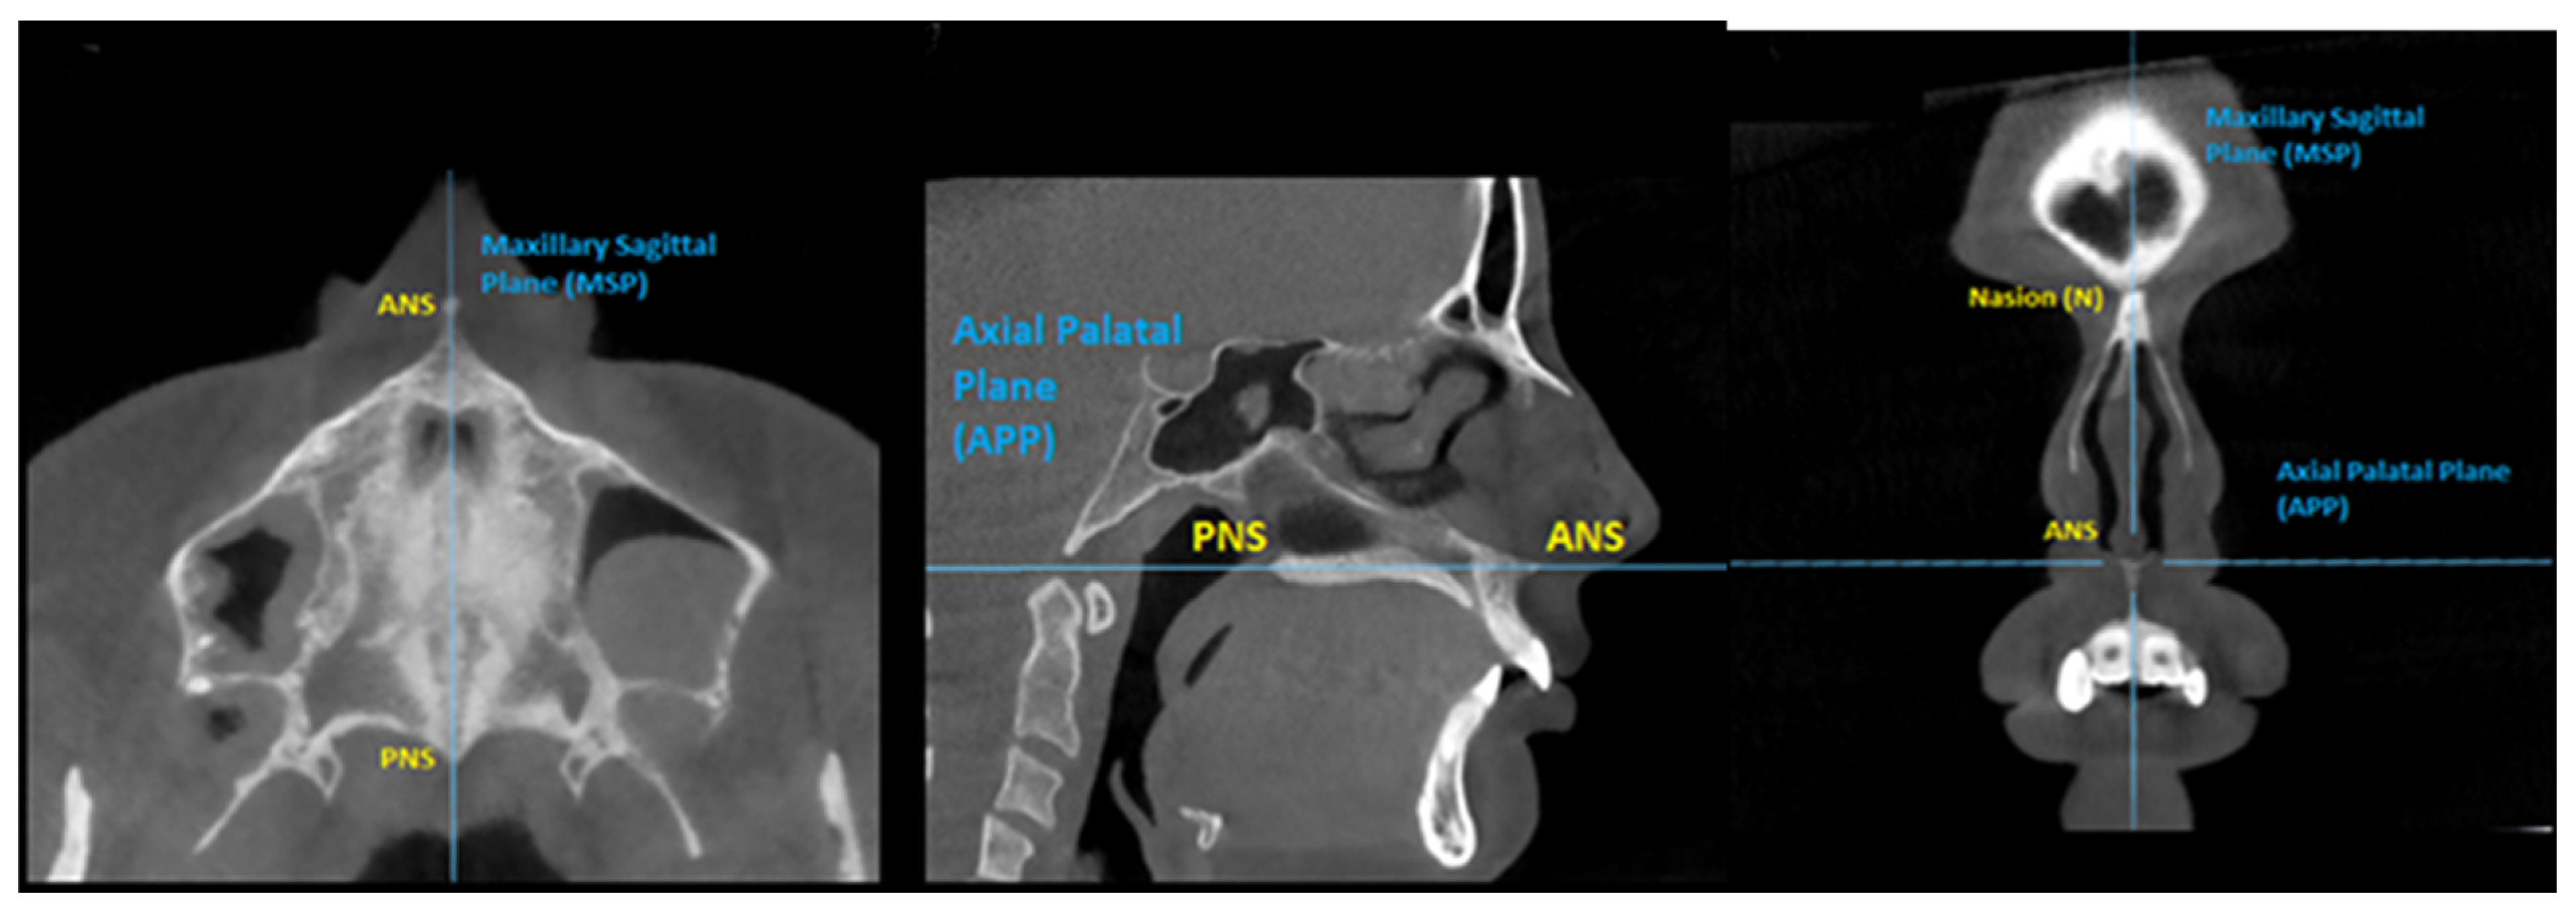

2.2. Evaluation Method

2.4. Three-Dimensional Visualization